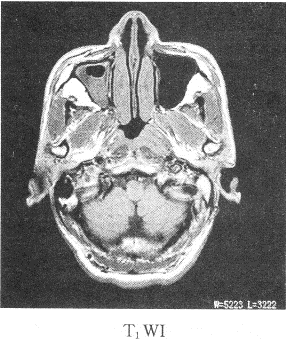

患者男性,39歲,因耳鳴,聽力下降來院,影像學(xué)檢查如圖所示

1.該患者最有可能的診斷是

正確答案:1.C;2.B;3.ABDE 解題思路:鼻咽癌我國以廣東省為高發(fā)地區(qū),男性多于女性,好發(fā)于鼻咽頂壁,其次為側(cè)壁,前壁和底壁極少。